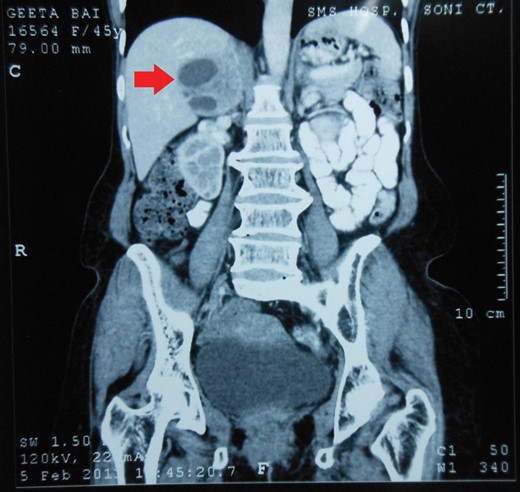

Routine laboratory tests were unremarkable. Ultrasound of the abdomen showed a 5 × 5 cm solid-cystic mass overlying the right kidney. CECT abdomen confirmed the presence of a right suprarenal tumour measuring 6 × 5 × 5 cm with solid-cystic components and fluid levels suggestive of intratumoural haemorrhage. Magnetic resonance imaging (MRI) of abdomen suggested an space occupying lesion in the right adrenal gland with multiple cystic spaces of variable sizes suggestive of pheochromocytoma. Fat planes to the adjacent structures were preserved with no evidence of metastases (Figs 1–4).

CECT abdomen showing an inhomogeneously dense right suprarenal mass (CORONAL SECTION).